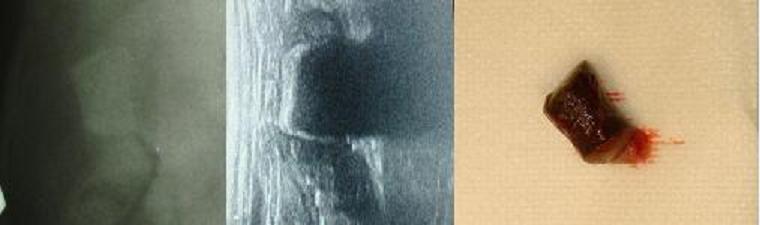

Na následujících snímcích je vyobrazeno cizí těleso jak bylo vidět na RTG snímku, na ultrasonografu a jak vypadalo reálně.

Cizí těleso-porovnání